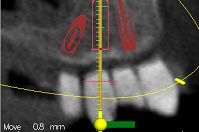

עקב חוסר בעצם ואי רצון מצד המטופל לעבור הרמות סינוס בוצע תיכנון ממוחשב של מיקום השתלים עוד בטרם ההשתלה.

ההשתלות בוצעו דרך שבלונה שהוכנה במדפסת תלת מימד בהתאם לקובץ הממוחשב.